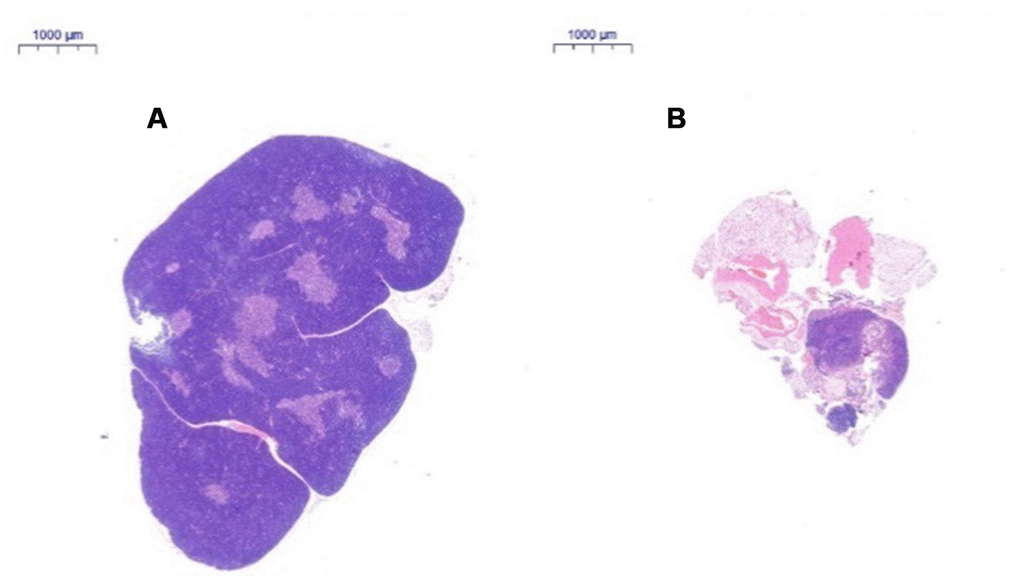

After HE staining, the tissue was observed by inverted microscopy. (1) HE staining of the thymus in 2-month-old C57 mice: A thin connective tissue envelope was observed on the surface of the thymus tissue, the thymocyte leaflet interval was not obvious, and the cortex and medulla were clearly defined. The thymus cells in the cortex were dense, and its coloration was deeper. The medulla contained more TECs and had lighter coloration. A large thymus were observed in young mice (Figure 3A). (2) HE staining of the thymus in 18-month-old C57 mice: The volume of the thymus was reduced, and the boundary of the cortex and medulla was not clear; most of the thymus tissue had been replaced by adipose tissue, and only a small portion of the cortex and medulla remained. A small number of lymphoid cells were scattered in the adipose tissue, which is a typical characteristic of old age (Figure 3B).

Figure 3. Changes in the thymus tissue structure in C57 mice of different ages. Note: (A) shows the thymus from a 2-month-old C57 mouse (20×); (B) shows the thymus from an 18-month-old C57 mouse (20×). HE staining of the thymus in 18-month-old C57 mice: the volume of the thymus was reduced, and the boundary of the cortex and medulla was not clear; most of the thymus tissue had been replaced by adipose tissue.